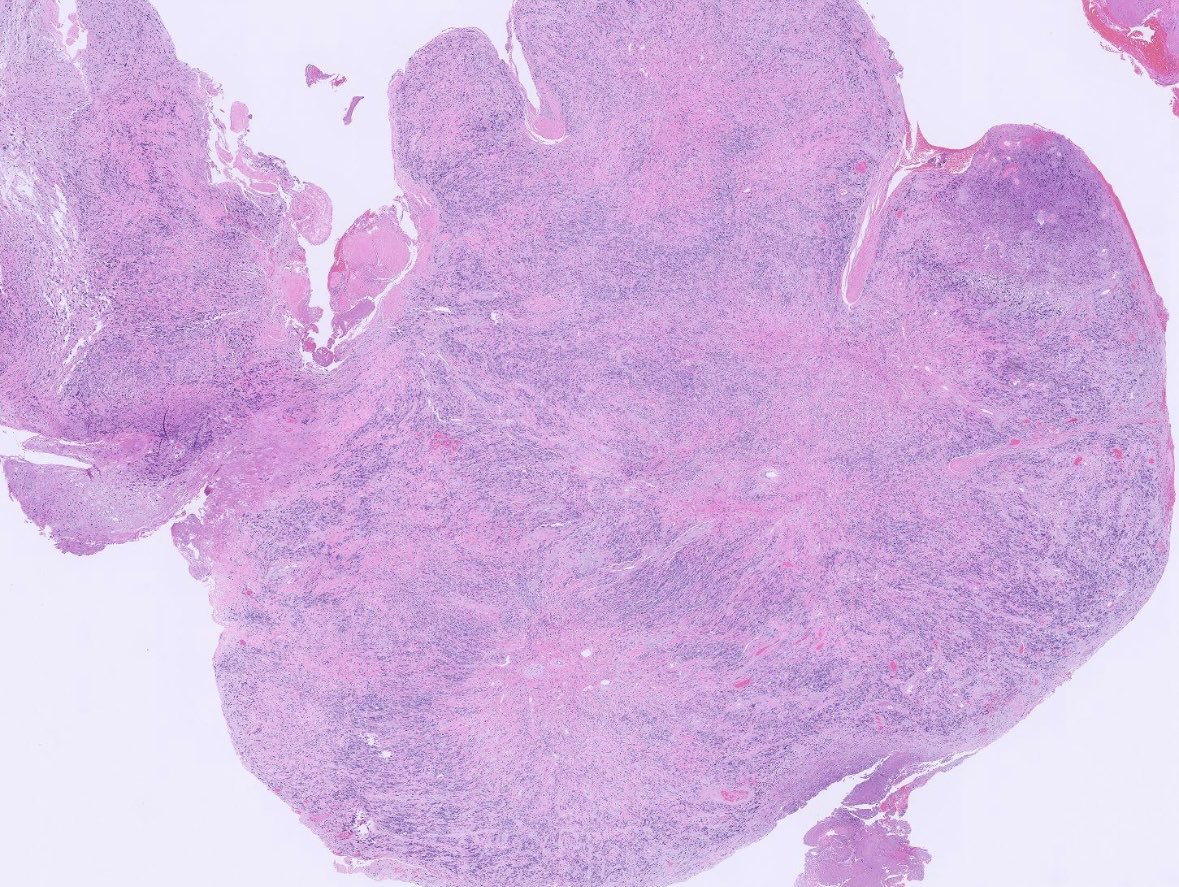

What is this thing? 65M meningeal mass. #pathtwitter #pathx #neuropath #neuropathology #cnspathology

7

16

40